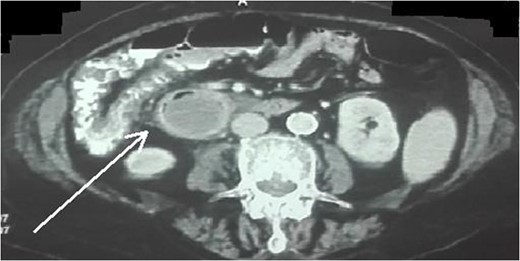

An 87-year-female patient was admitted to emergency department complaining about vomiting for the past 7 days with mild abdominal pain. The patient was hemodynamically stable, had sluggish bowel sounds and soft abdominal wall with mild tenderness. The patient also suffered from atrial fibrillation, heart failure, myelodysplastic syndrome, hiatus hernia and cholelithiasis. The findings of the laboratory tests were unremarkable. Plain chest and abdominal radiograms revealed hiatus hernia with gastric dilation (Fig. 1), a few air-fluid levels and pneumobilia, with delineation of extrahepatic and intrahepatic bile ducts by air (Fig. 2). A nasogastric tube was inserted, which drained biliary content. An abdominal computed tomography (CT) scan revealed the presence of air in the intrahepatic bile ducts, free air and leakage of oral contrast agent in the hepatic hilum and subhepatic space and an impacted gallstone in the third portion of the duodenum (Figs 3 and 4). The diagnosis of cholecystoenteric fistula and proximal gallstone ileus was set.

Abdominal CT scan (axial plane). The arrow shows the impacted gallstone.